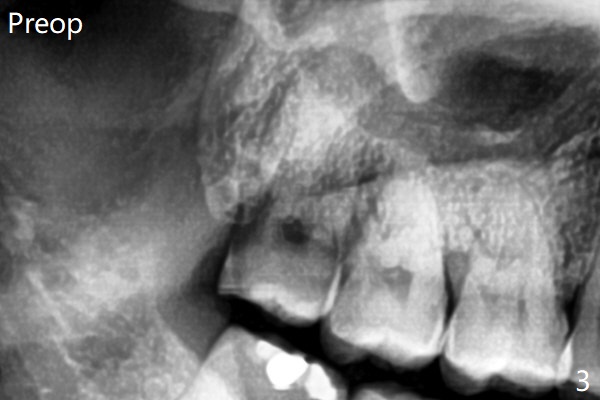

The bone density is high post #1 extraction (Fig.6 (left panel)), related to difficult removal (DB root tip fracture). It appears that bone graft at #16 (^) remains in place 15 months postop.